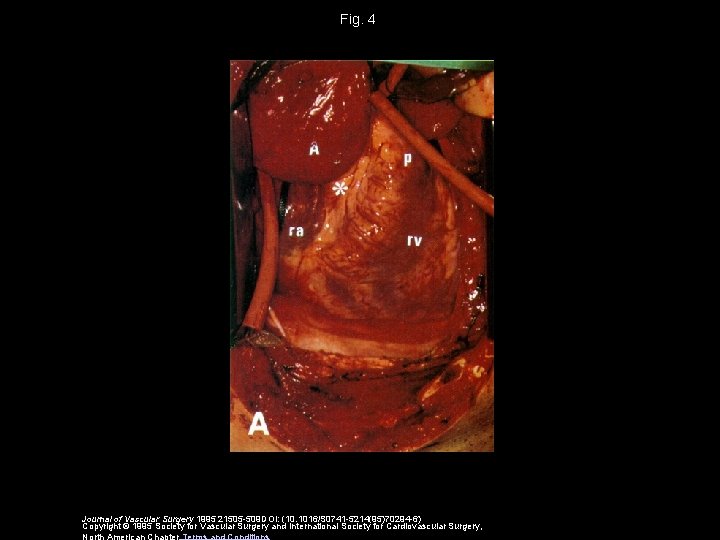

Fig. 4 Journal of Vascular Surgery 1995 21505 -509 DOI: (10. 1016/S 0741 -5214(95)70294 -6) Copyright © 1995 Society for Vascular Surgery and International Society for Cardiovascular Surgery, North American Chapter Terms and Conditions